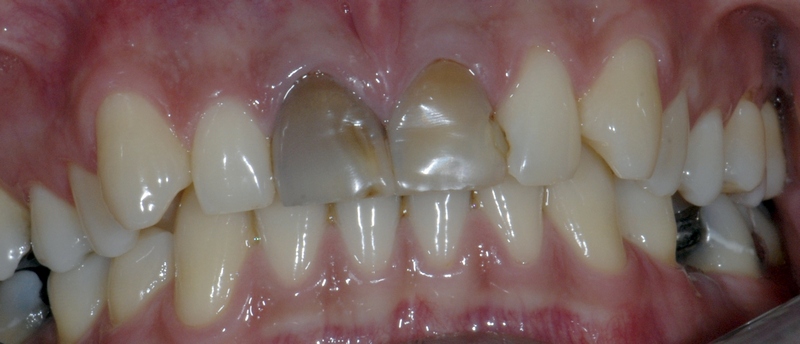

Dentalna protetika - krunice, mostovi, proteze

Vrhunska optička estetska i mehanička svojstva bezmetalnih keramičkih radova